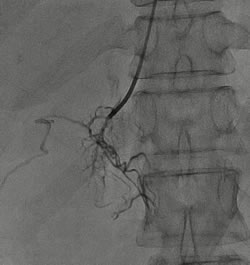

左侧肾上腺静脉插管采血 右侧肾上腺静脉插管采血